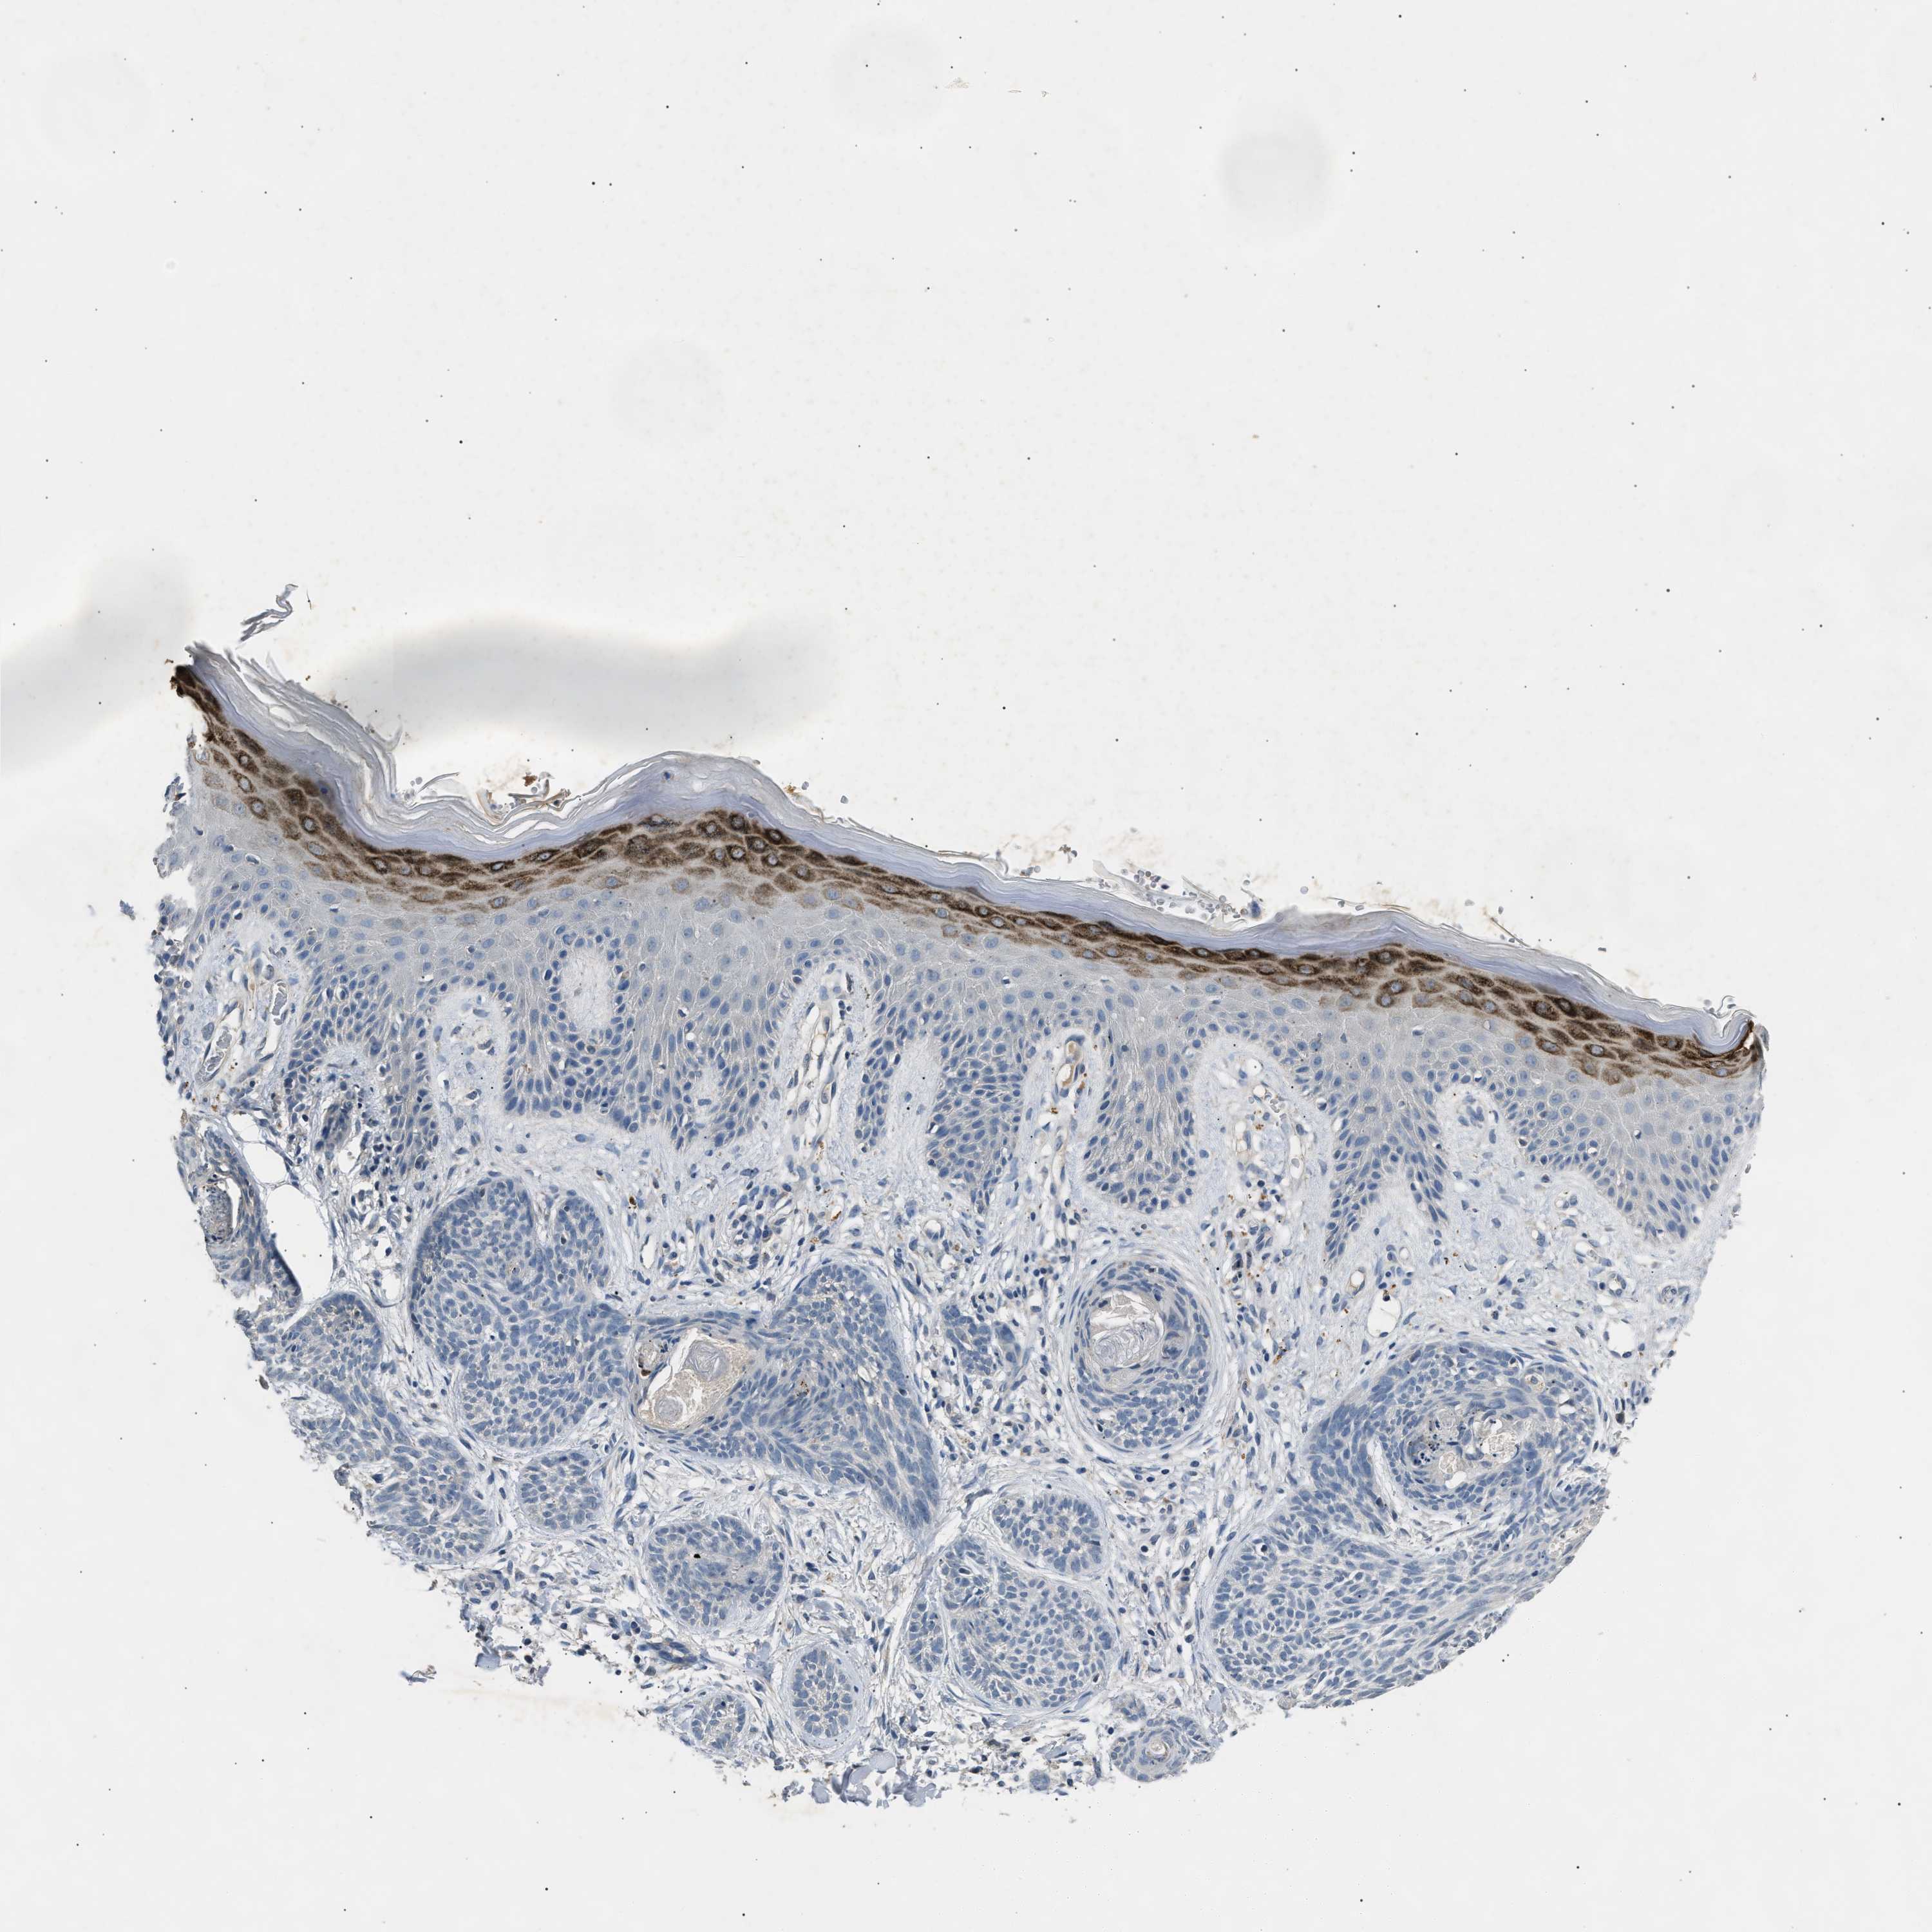

SKIN CANCER - Protein expressioni

A mouse-over function shows sample information and annotation data. Click on an image to view it in a full screen mode. Samples can be filtered based on level of antibody staining by selecting one or several of the following categories: high, medium, low and not detected. The assay and annotation is described here.

Antibody stainingi

Antibody staining in the annotated cell types in the current human tissue is reported as not detected, low, medium, or high, based on conventional immunohistochemistry profiling in selected tissues. This score is based on the combination of the staining intensity and fraction of stained cells.

Each image is clickable and will lead to virtual microscopy that enables deeper exploration of all samples and also displays staining intensity scores, fraction scores and subcellular localization as well as patient and tissue information for each sample.

Antibody HPA019141

Antibody CAB000047

Staining

High

Medium

Low

Not detected

Intensity

Strong

Moderate

Weak

Negative

Quantity

>75%

75%-25%

<25%

None

Location

Nuclear

Cytoplasmic/membranous

Cytoplasmic/membranous,nuclear

Squamous cell carcinoma in situ, NOS